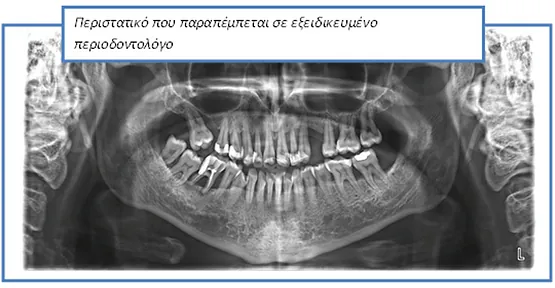

Στις μέρες μας, ένα μικρό ποσοστό του πληθυσμού εμφανίζει βαριά περιοδοντική καταστροφή και επομένως χρειάζεται απόλυτα εξειδικευμένες υπηρεσίες.

Οι περισσότεροι από εμάς χρειάζονται περιοδοντολογική φροντίδα, δηλαδή πρόληψη και θεραπεία νόσων – λοιμώξεων που προέρχονται από μικροοργανισμούς που στην πλειονότητα των περιπτώσεων βρίσκονται στο στόμα μας.

Περιστατικά που αντιμετωπίζονται στο ιατρείο μας

Στο ιατρείο ακολουθείται το νεότερο και πλέον σύγχρονο πρωτόκολλο θεραπείας (GBTguidedbiofilmtherapy), σύμφωνα με το οποίο ο οδοντιατρικός καθαρισμός, η θεραπεία ουλίτιδας και η περιοδοντική θεραπεία στη φάση ελέγχου της φλεγμονής και διατήρησης του αποτελέσματός της, πραγματοποιούνται με το πιο αποτελεσματικό, ήπιο και ελάχιστα επεμβατικό τρόπο.